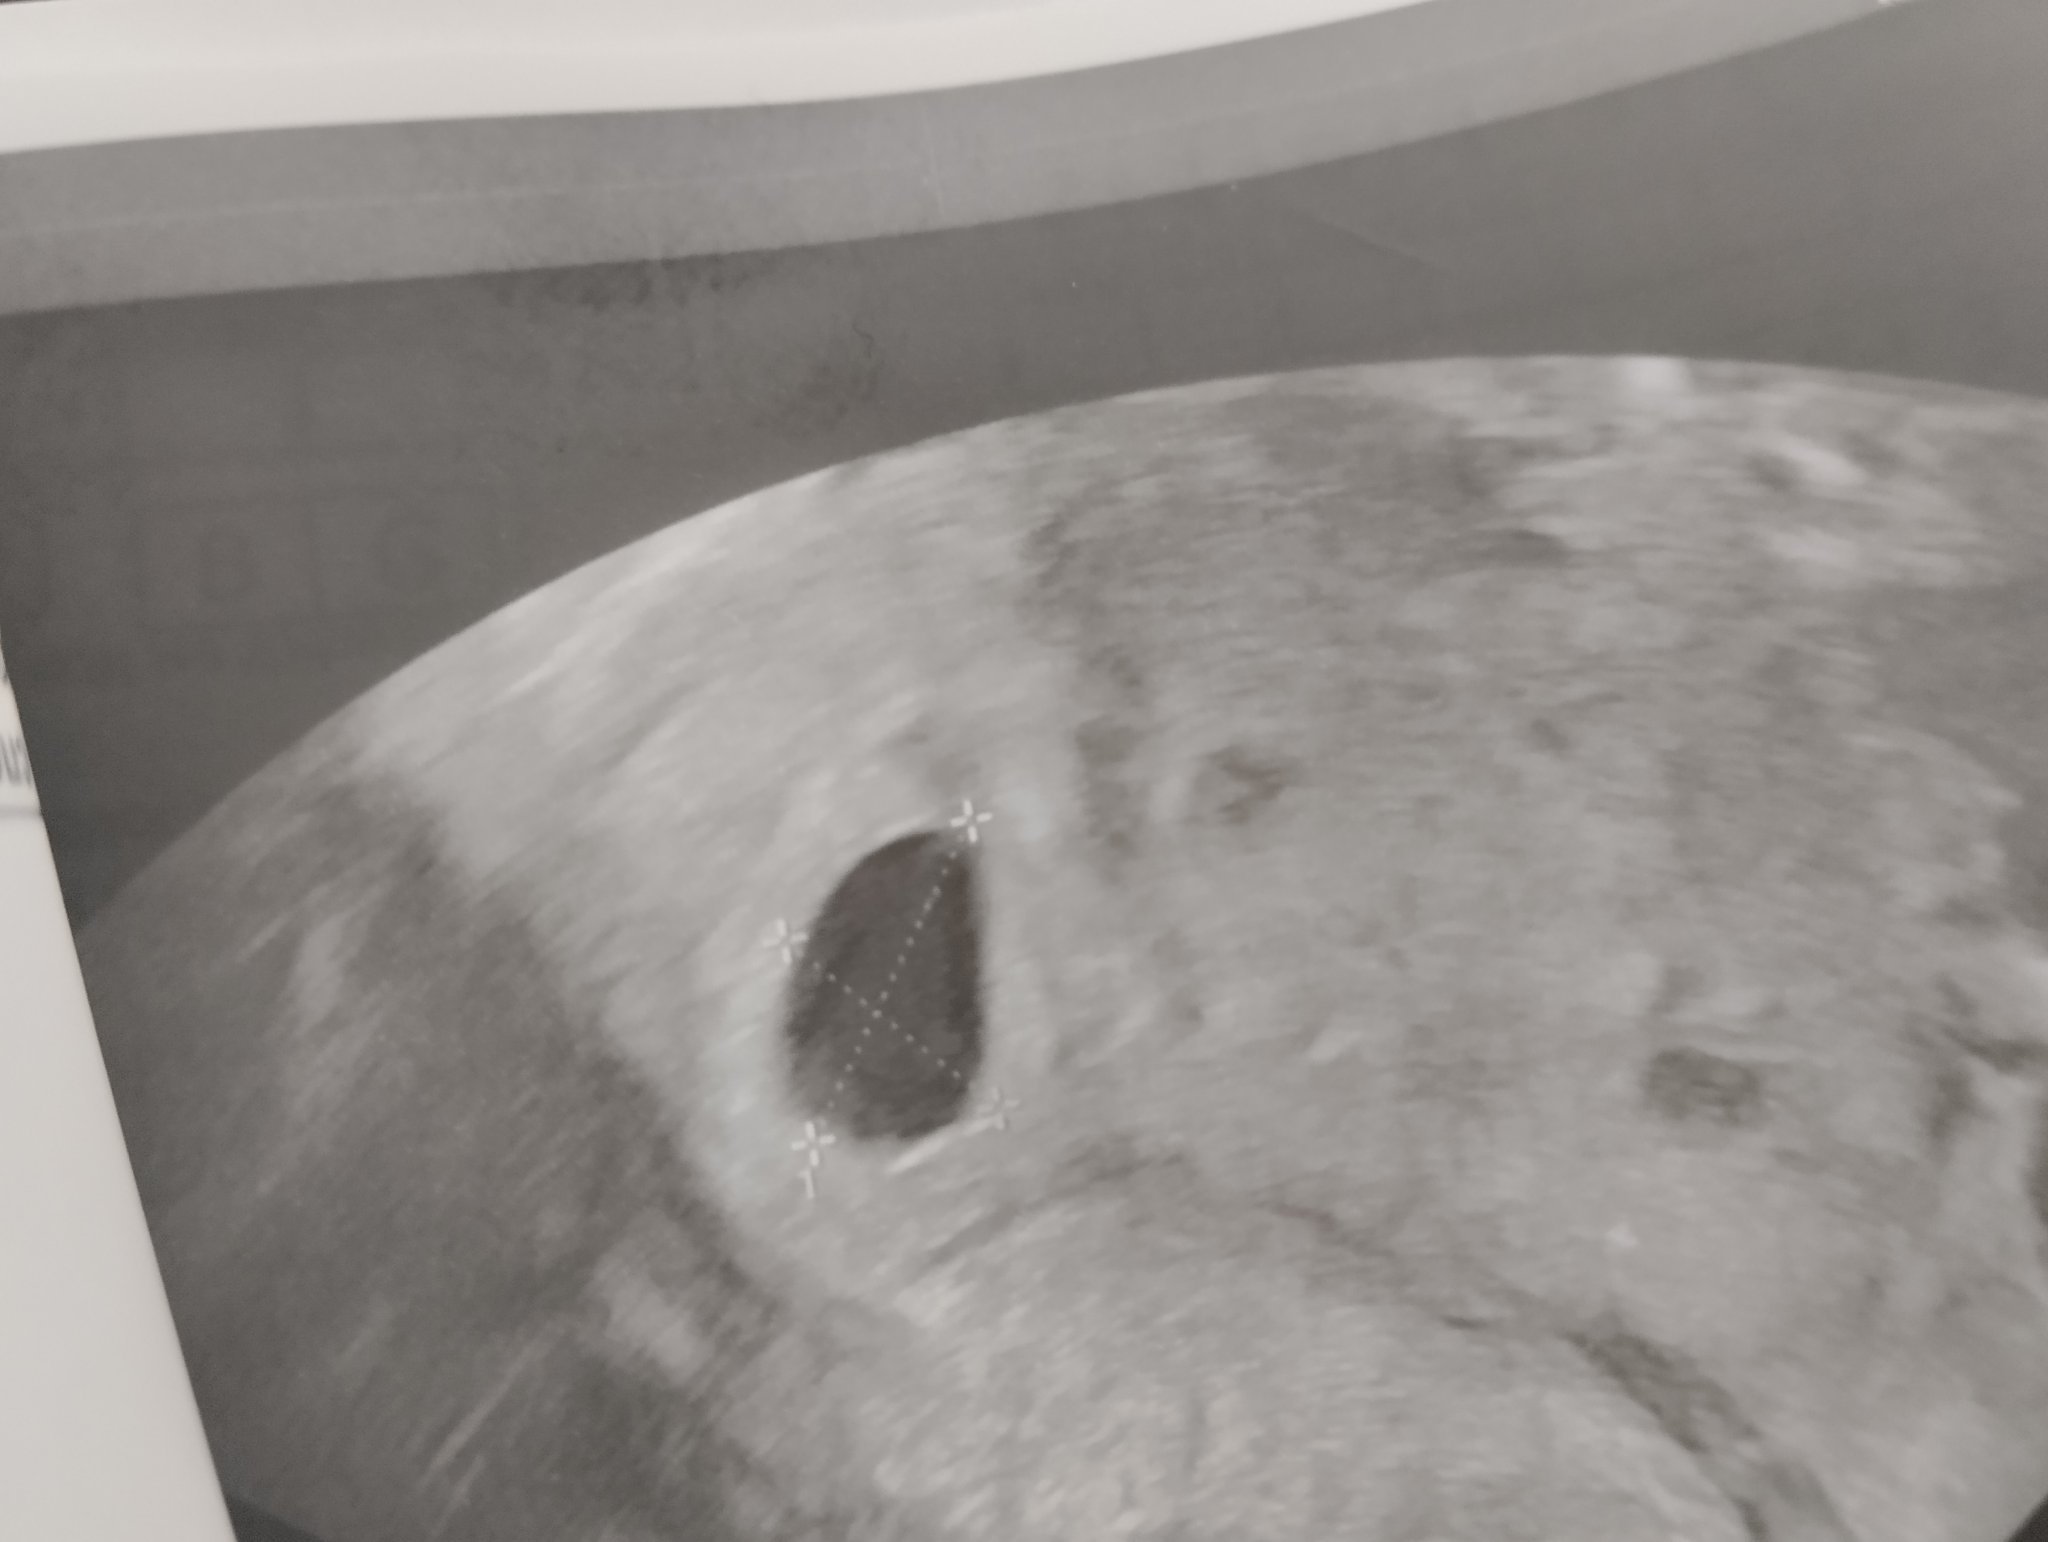

Към днешна дата и при тази стойност следва да има сакче с ясно изразена ембрионална структура.

Ето такова нещо (при вглеждане се вижда ембрионалната маса ниско долу в сакчето - това е снимка на най-малкият ми син на денят, в който е днес Злати):

-  в 5+3/5+4 трябва да се вижда вътрематочна бременност. Аз на последните снимки не виждам нищо такова. Така изглеждаше моята двуплоднна бременност в 5+3. Не можеш да го сбъркаш: